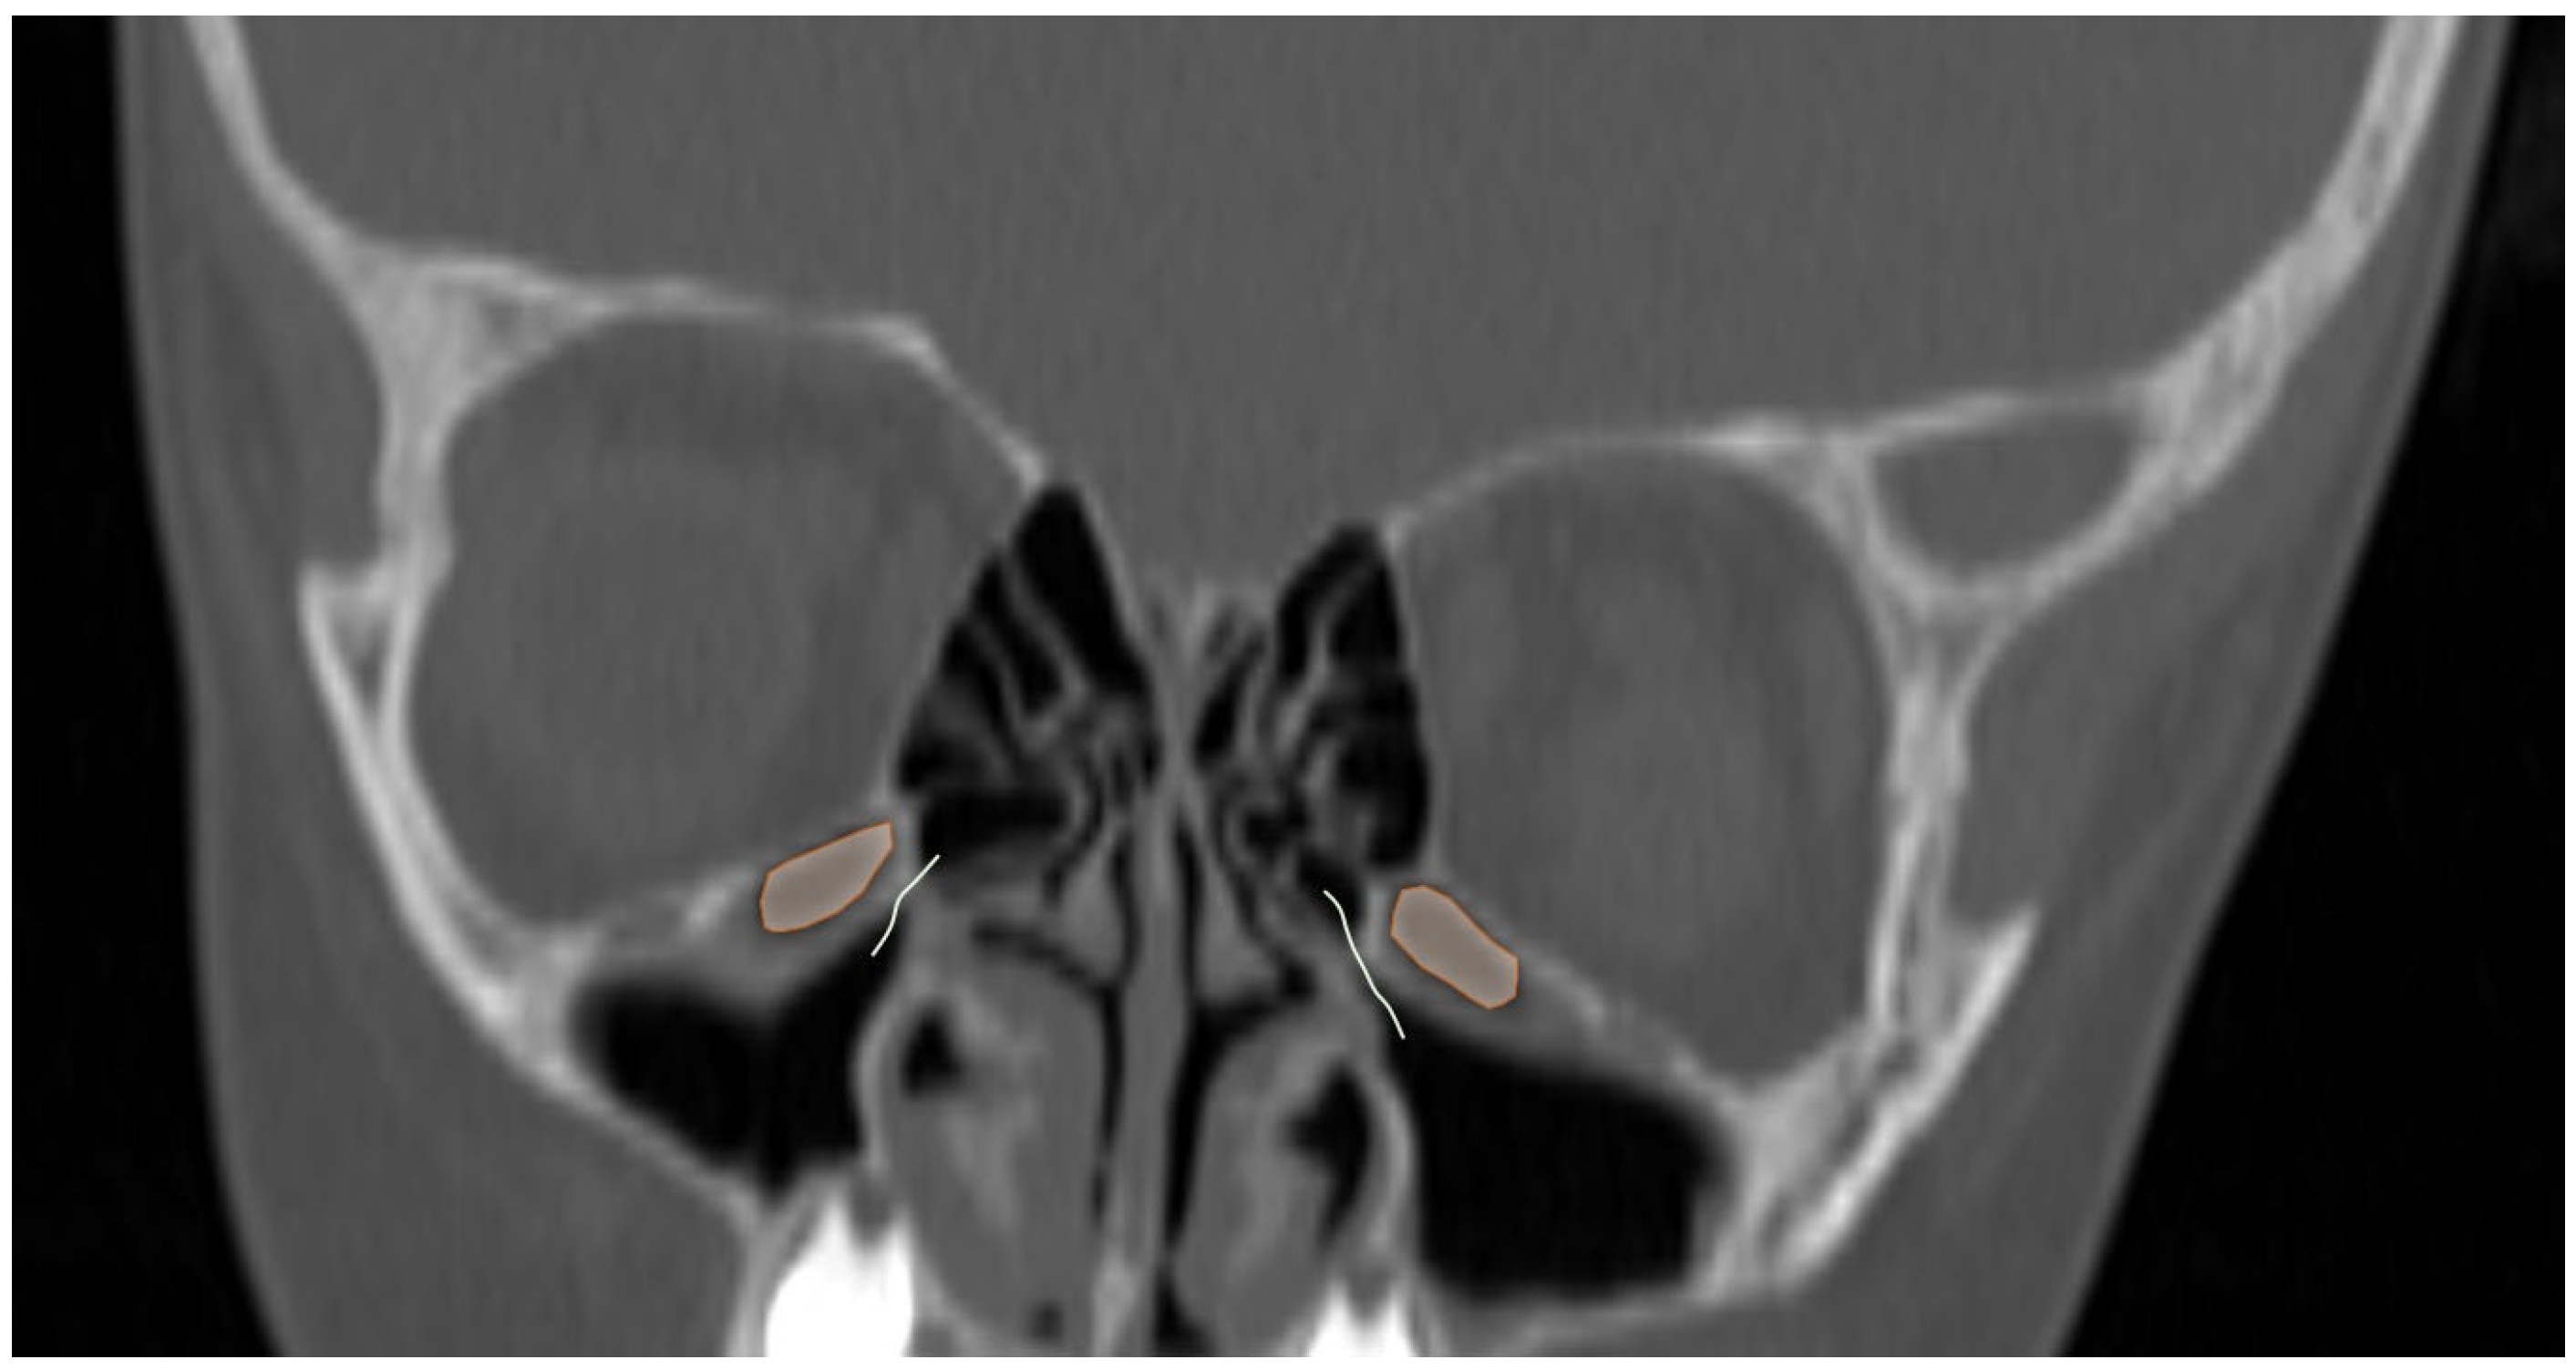

3.2. Sinonasal Variations